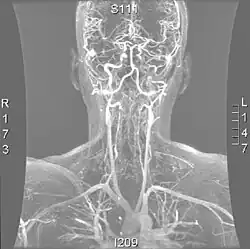

Magnetic resonance angiogram of the neck vessels in a person with Ehlers-Danlos syndrome type IV; it shows a dissection of the left internal carotid artery, dissection of both vertebral arteries in their V1 and V2 segments and a dissection of the middle and distal third of the right subclavian artery. Such striking episodes of dissection are typical for this "vascular" subtype of Ehlers-Danlos syndrome.

Various diagnostic modalities exist to demonstrate blood flow or absence thereof in the vertebral arteries. The gold standard is cerebral angiography (with or without digital subtraction angiography).[3][18][19] This involves puncture of a large artery (usually the femoral artery) and advancing an intravascular catheter through the aorta towards the vertebral arteries. At that point, radiocontrast is injected and its downstream flow captured on fluoroscopy (continuous X-ray imaging).[20] The vessel may appear stenotic (narrowed, 41–75%), occluded (blocked, 18–49%), or as an aneurysm (area of dilation, 5–13%). The narrowing may be described as "rat's tail" or "string sign".[1] Cerebral angiography is an invasive procedure, and it requires large volumes of radiocontrast that can cause complications such as kidney damage.[20] Angiography also does not directly demonstrate the blood in the vessel wall, as opposed to more modern modalities.[1][2] The only remaining use of angiography is when endovascular treatment is contemplated (see below).[1]

More modern methods involve computed tomography (CT angiography) and magnetic resonance imaging (MR angiography). They use smaller amounts of contrast and are not invasive. CT angiography and MR angiography are more or less equivalent when used to diagnose or exclude vertebral artery dissection.[18] CTA has the advantage of showing certain abnormalities earlier, tends to be available outside office hours, and can be performed rapidly.[1] When MR angiography is used, the best results are achieved in the T1 setting[2] using a protocol known as "fat suppression".[1][2][3] Doppler ultrasound is less useful as it provides little information about the part of the artery close to the skull base and in the vertebral foramina, and any abnormality detected on ultrasound would still require confirmation with CT or MRI.[1][2][3]